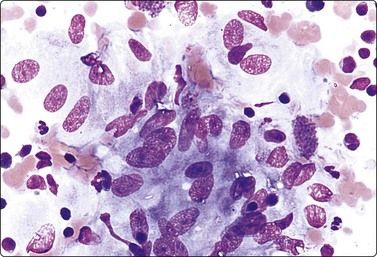

Hepatocellular carcinoma (Figs 10.14-10.27)

image

Fig. 10.14 Hepatocellular carcinoma

Cellular smears with irregular large fragments, clusters and dispersed cells (H&E, LP).

image image

Fig. 10.15 Hepatocellular carcinoma

(A) Cells are typically arranged in widened trabeculae (Pap, IP); (B) Less commonly in acinar arrangements (cell block H&E, IP).

Fig. 10.16 Hepatocellular carcinoma

A reticulin stain on cell block sections may highlight (A) widened trabeculae and/or acinar structures (Reticulin, HP); (B) reduced or absent reticulin (cell block reticulin, HP).

Fig. 10.17 Hepatocellular carcinoma

Tissue fragment of malignant cells traversed by spindle endothelial cells representing capillary blood vessels (A, Pap, IP; B, MGG, HP).

Fig. 10.18 Hepatocellular carcinoma

Endothelial cell envelopes seen as thin spindle nuclei surrounding tumor fragments (H&E, HP).

Fig. 10.19 Hepatocellular carcinoma

The cells resemble hepatocytes, but are larger with increased nucleocytoplasmic ratios; tumor cells have round nuclei and central large nucleoli; note cluster of benign hepatocytes (to right in A) (A, Pap, HP; B, MGG, HP).

Fig. 10.20 Hepatocellular carcinoma

Multiple large round atypical nuclei stripped of their cytoplasm; one or multiple macronucleoli (MGG, HP).

Fig. 10.21 Hepatocellular carcinoma

Moderately differentiated tumor with characteristic nuclear morphology; numerous green/black bile thrombi between tumor cells (MGG, HP).

Fig. 10.22 Hepatocellular carcinoma

‘Clear cell’ variant; large cells with abundant pale vacuolated cytoplasm, large vesicular nuclei, large nucleoli (Pap, HP).

image image image

Fig. 10.23 Hepatocellular carcinoma, fibrolamellar type

(A) Neoplastic cells adherent to fragments of lamellar collagen (MGG, HP); (B) Very large, malignant hepatocytes with prominent nucleoli and abundant granular cytoplasm (MGG, HP oil); (C) Corresponding tissue section (H&E, IP).

Fig. 10.24 Hepatocellular carcinoma

Well-differentiated tumor composed of poorly cohesive hepatocytic cells with mild anisokaryosis but large nucleoli; differentiation from adenoma difficult (MGG, HP).

Fig. 10.25 Hepatocellular carcinoma

CD34 immunostaining demonstrates the classic endothelial staining pattern which is absent in reactive liver cell block (CD34, HP).

Fig. 10.26 Hepatocellular carcinoma

(A) pCEA immunostaining shows cytoplasmic staining along canalicular luminal edges only (pCEA, HP); (B) HepPar-1 produces diffuse granular cytoplasmic staining in distinction to adenocarcinoma, which is negative (HepPar-1, HP).

Fig. 10.27 Cholangiocarcinoma

(A) Disorganized clusters of irregular but not very pleomorphic tumor cells with pale cytoplasm and relatively small nuclei (MGG, HP); (B) Disorganized cluster of mildly pleomorphic epithelial cells with hyperchromatic nuclei and prominent nucleoli (MGG, HP); (C) Corresponding tissue section (H&E, IP).

Criteria for diagnosis

Cellular smears,

Neoplastic cells forming widened trabeculae, acini or multilayered sheets,

Endothelial cells lining cell groupings or small capillaries transgressing clusters of tumor cells,

Polygonal cells with increased N : C ratio,

Central round nuclei often with macronucleoli,

Increased nuclear size and atypia with binucleation and multinucleation,

Scant to abundant eosinophilic, granular cytoplasm; may be vacuolated,

Dispersed cells including many atypical stripped nuclei,

Intranuclear cytoplasmic inclusions,

Intracytoplasmic eosinophilic fibrillary inclusions (hyaline bodies),

Intracytoplasmic bile pigment and/or bile plugs between cells, green or yellow in Papanicolaou smears and greenish-black with MGG,

Frequent mitoses,

Bile duct epithelium absent,

Loss of above characteristics with dedifferentiation.

The characteristic findings relate to (1) cell groupings, (2) relationship to endothelium and (3) cell morphology.39,41,72,79,116-132

The features in any individual FNA sample are extremely variable and largely dictated by tumor differentiation.116,117,127,132 As the degree of differentiation decreases, the cells become more obviously malignant and their resemblance to hepatocytes decreases.

Smears are typically cellular with large fragments, clusters and dispersed cells (Fig. 10.14). Cell groupings are classically trabecular (Fig. 10.15A), particularly in better-differentiated tumors. Acinar arrangements may be seen in up to 40% of HCC (Fig. 10.15B).72 With decreasing differentiation, smaller sheets and single-lying cells become more frequent. A reticulin stain on smears or cell block material may highlight the widened trabeculae and/or acinar structures or the reduced or absent reticulin (Fig. 10.16). Endothelial relationships to HCC cell groups are an integral part of the diagnosis. Endothelial cells of sinusoidal capillaries may traverse (Fig. 10.17) or enclose (Fig. 10.18) trabeculae or separate tumor cell groupings.128 This important diagnostic criterion is diminished and then lost with decreasing differentiation.

The cells resemble hepatocytes, thus demonstrating polygonal outlines and dense, granular cytoplasm, but with increased nucleocytoplasmic ratios over normal counterparts (Fig. 10.19). Centrally placed nuclei, characterized by granular to coarse chromatin, show cytoplasmic invaginations (intranuclear inclusions) in up to 70% of cases and large central nucleoli in up to 60% of cases. One of the most outstanding cytological appearances in HCC is the presence of many stripped malignant nuclei with identical characteristics, lying free in the background between cell groups (Fig. 10.20).126 The presence among malignant cells of occasional tumor giant cells or of bizarre hepatocytes would seem to favor primary liver carcinoma as they are rare in metastatic carcinoma.72,131 Bile pigment within the cytoplasm and between the cells proves the hepatocellular origin of the tumor, but is demonstrable in only 25% of cases (Fig. 10.21). Fouchet’s reagent counterstained with hematoxylin/Sirius red stains bile intensely green (Fig. 2.19). Contaminant benign hepatocytes and bile duct epithelium may be collected from the surrounding non-neoplastic liver, particularly in the setting of cirrhosis. They usually lie apart from the tumor cells.